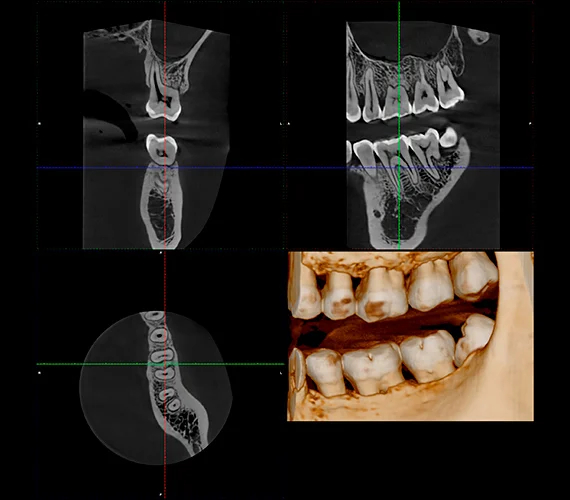

Tryb Endo do precyzyjnego obrazowania

Rozdzielczość endodontyczna 75 μm w systemie Planmeca Viso G1 umożliwia doskonałą wizualizację nawet najdrobniejszych szczegółów anatomicznych. Wyraźna jakość obrazu to idealny wybór w przypadku leczenia endodontycznego oraz w innych sytuacjach wymagających oglądania obszaru zainteresowania z bliska. Obrazy można dodatkowo poprawić, stosując opartą na AI optymalizację szumów Planmeca NOA™.